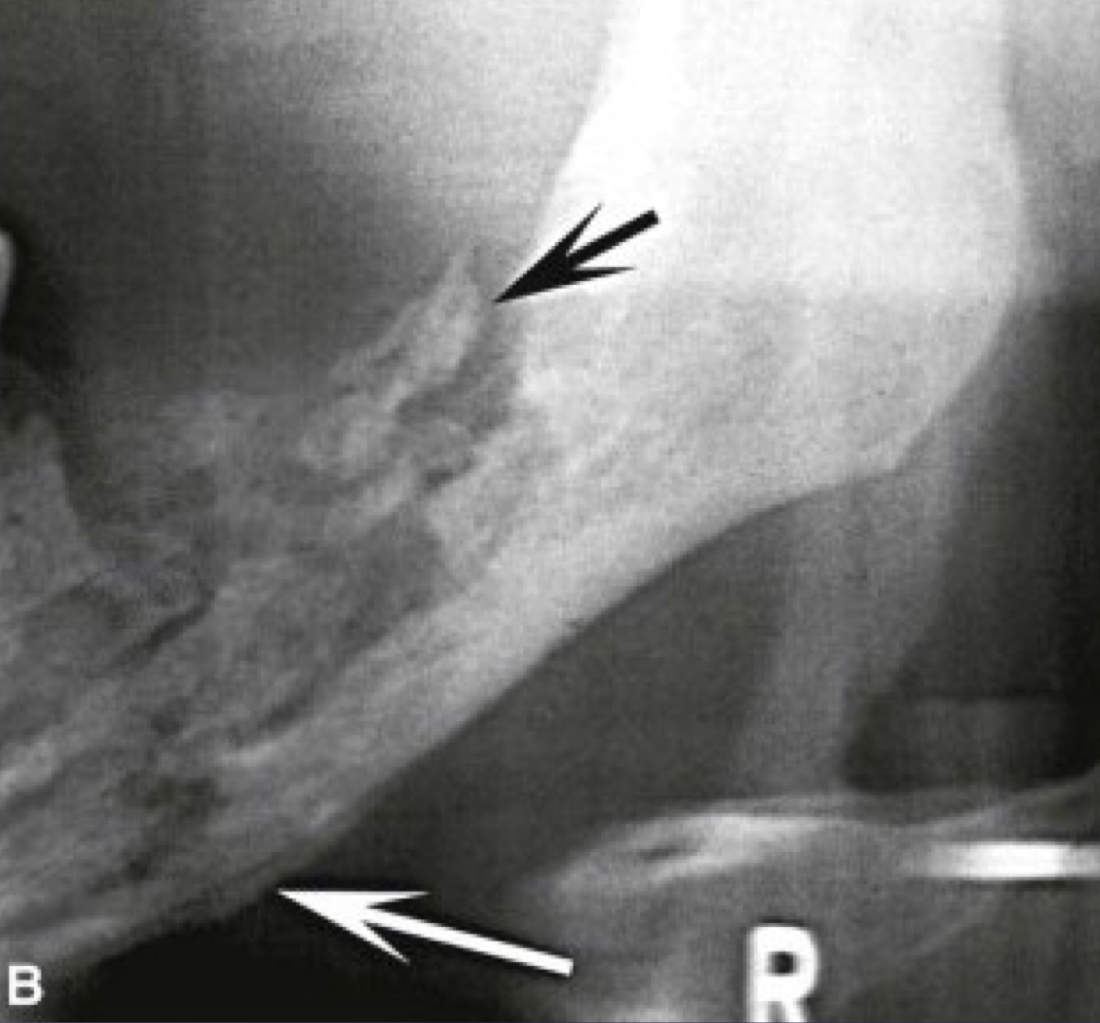

white and black arrow

which imaging is method of choice for seeing internal structure (sequestrea) of acute osteomyelitis?

periosteal reaction

new bone formation parallel to the cortex (almost looks like periosteum lifted and bone under)